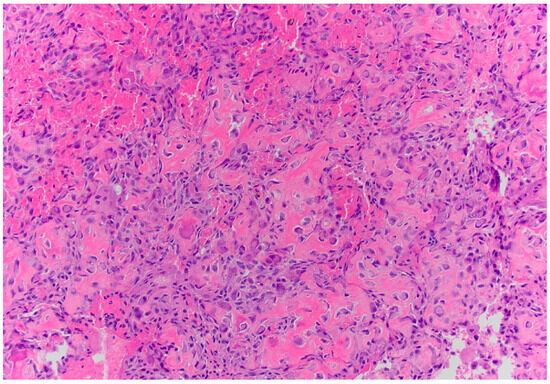

Pathology described an atypical eosinophilic osteoid-secreting lesion containing abundant osteoblasts with vascular structures, consistent with an osteoblastoma. There was no malignant mitotic activity identified. However, it was not possible to rule out osteosarcoma, making the differential diagnosis at that time osteoblastic osteosarcoma vs. aggressive osteosarcoma (Figure 2).

Figure 2. Pathology demonstrates an atypical eosinophilic osteoid-producing lesion (H and E, 400×).